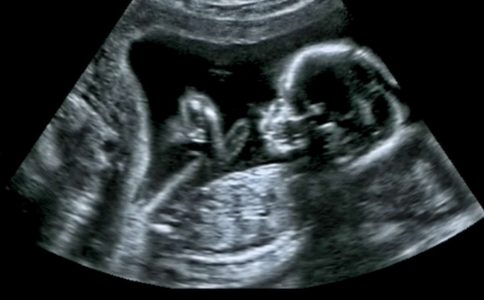

Παρά το γεγονός ότι η εν λόγω διαδικασία επιτρέπεται για ζευγάρια που αποδεδειγμένα αδυνατούν να τεκνοποιήσουν, αυτό που βαραίνει περισσότερο στο ισοζύγιο της συζήτησης είναι ότι, προκειμένου να μπορέσει να τεκνοποιήσει μια γυναίκα, μια άλλη γυναίκα μετατρέπεται σε ζωντανό εμπόρευμα. Και αυτή η γυναίκα που μετατρέπεται σε εμπόρευμα είναι ένας άνθρωπος που χρειάζεται χρήματα.

Φαντάζομαι δεν θα υπάρχει ούτε μία εύπορη γυναίκα που να είναι διατεθειμένη να κυοφορήσει και να γεννήσει ένα παιδί για μια άγνωστη. Μας αρκούν εδώ τα φιλελεύθερα περί αυτοδιάθεσης του σώματος ή μήπως ισχύει το «όπου φτωχός και η μοίρα του»;

Είναι η βιολογική διαφορετικότητα αδυναμία; Ή μήπως η βιολογική αδυναμία είναι κοινωνικά κατακριτέα; Τίποτε από τα δύο δεν θα έπρεπε να ισχύει. Αυτό, όμως, δεν σημαίνει ότι νομιμοποιούμαστε, πληρώνοντας, να κάνουμε χρήση ενός τρίτου ανθρώπου για να γίνουμε βιολογικοί γονείς με το ζόρι. Υπάρχει, άλλωστε, και ο δρόμος της υιοθεσίας.